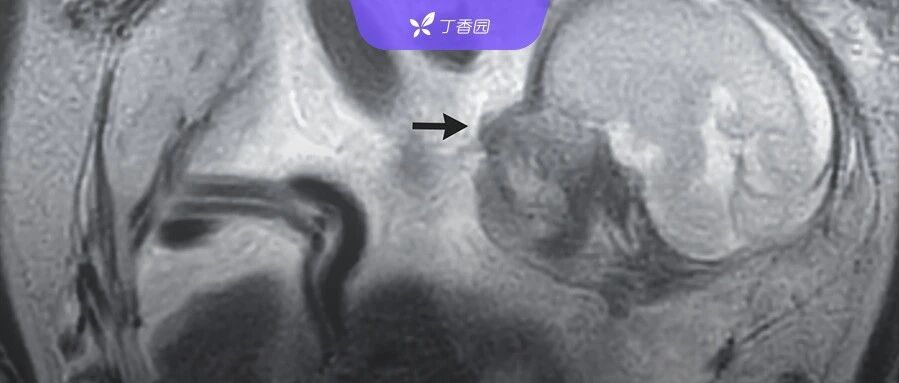

| 患者剧烈腹痛,腹腔里发现 6 个月大胎儿…还顺利生下来了! | 查看 | 2023-12-28 14:12:22 | 55540 | 14 | 2023-12-28 15:13:31 | 丁香园 | |